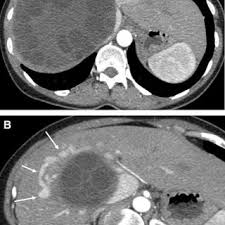

Chiasmata -mə-tə or chiasmas also chiasms 1. Esophageal varices are extremely dilated sub-mucosal veins in the lower third of the esophagus. Located in metro Denver northern Colorado and western Nebraska serving all of the Front Range our team consists of board-certified and fellowship-trained interventional radiologists. This results in hepatic congestion similar to Budd-Chiari syndrome and post-sinusoidal portal hypertension. The patients condition should be monitored throughout the procedure. They are most often a consequence of portal hypertension commonly due to cirrhosis. Toxic injury to liver sinusoids causes sloughing of endothelial cells that embolize to hepatic venules and cause eventual fibrosis of the venules. Coin in the Esophagus. There is no clear consensus regarding the number of occluded veins some authors claim that there should be at least one occluded hepatic vein 7 others state that there are no significant.

Carcinoma of the Colon. Budd-Chiari syndrome a blockage in one or more veins that carry blood from the liver back to the heart. And coumarin skin necrosis adrenal gland hemorrhage and infarction. Toxic injury to liver sinusoids causes sloughing of endothelial cells that embolize to hepatic venules and cause eventual fibrosis of the venules. Chiari malformation CM is a structural defect in the cerebellum characterized by a downward displacement of one or both cerebellar tonsils through the foramen magnum the opening at the base of the skull. Embolism and thrombosis of. La présence dune ou plusieurs affections prothrombotiques est fréquente La prise en charge repose sur un traitement anticoagulant précoce le traitement de l.